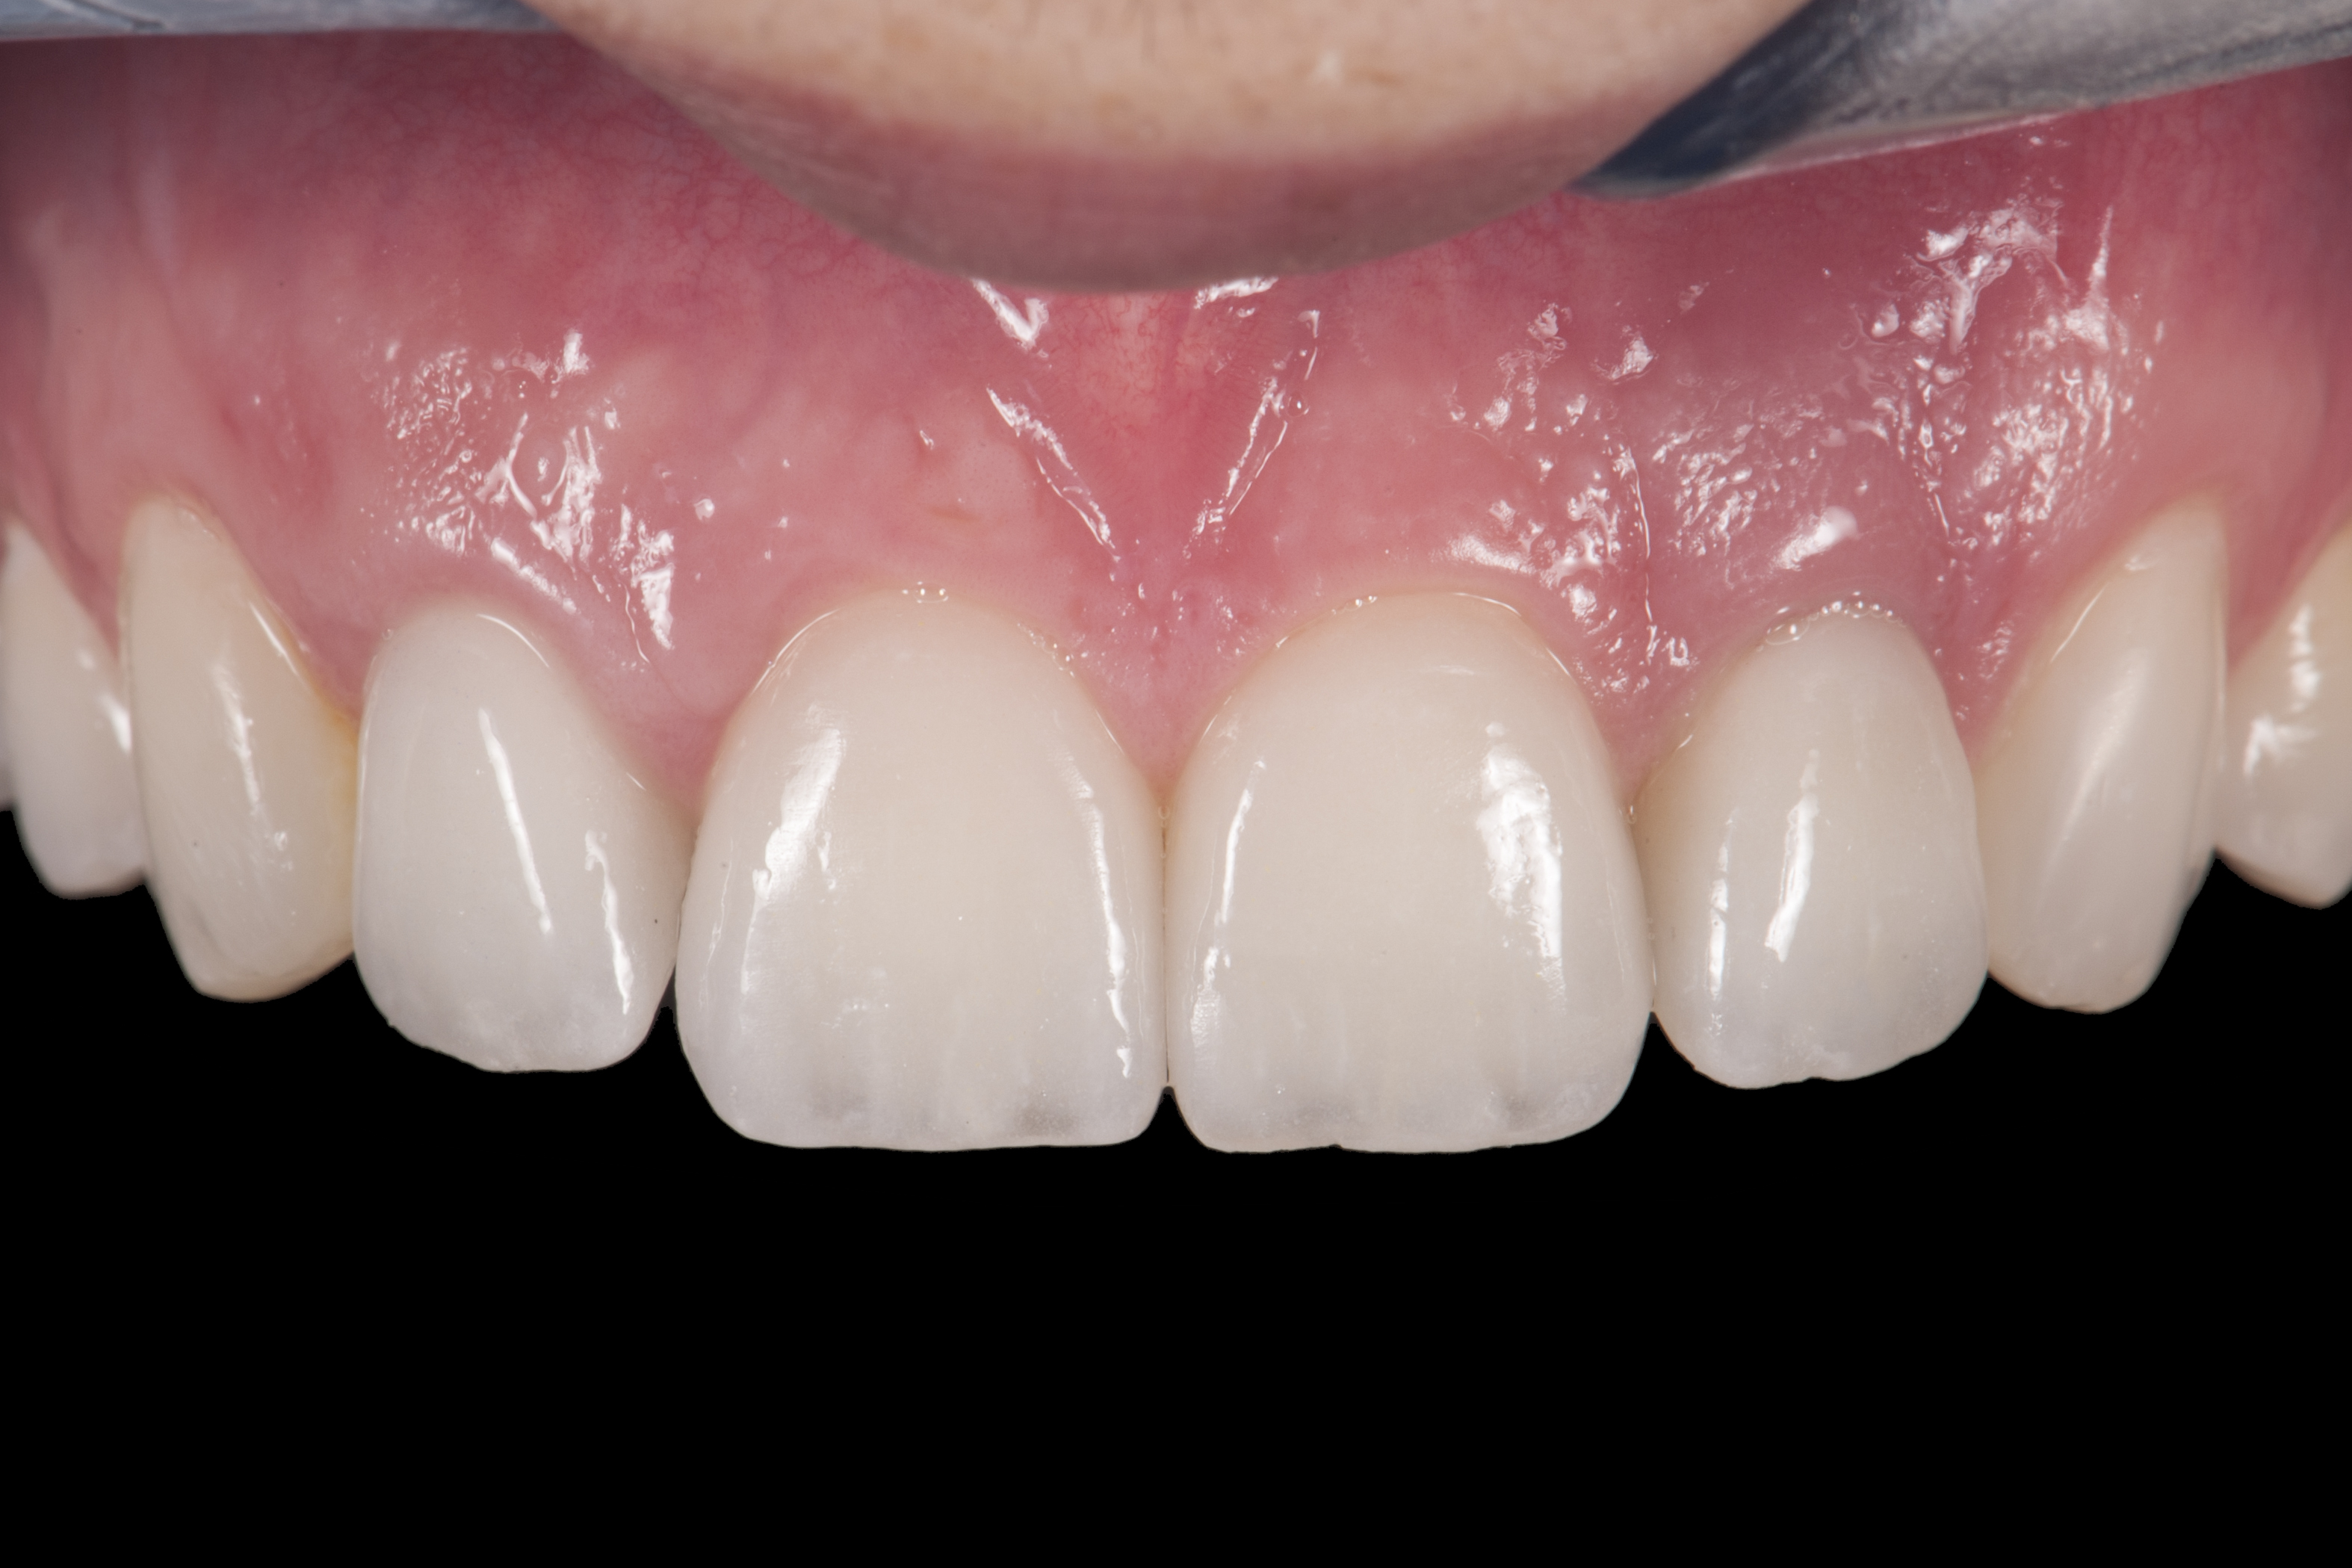

(20.) Facial view of final single-wing, modified zirconia resin-bonded bridges.

Figure 20

When the patient returned, the fit was evaluated in the mouth. Once verified, the internal surface of the framework was etched with a 9.5% hydrofluoric acid for 90 seconds and then salinized. After etching the enamel surface with phosphoric acid for 30 seconds and applying the primer (Single Bond Plus, 3M ESPE) to both the internal surface of the framework and the enamel, the zirconia bridge was bonded with a dual-cure resin cement (RelyX™ ARC, 3M ESPE). After the procedure, the patient ended up with a long-term, high-strength esthetic restoration advantaged by the bonding potential of fledspathic ceramic (Figure 20 through Figure 24). Six years after placement, the prosthesis had remained in place with no complications.